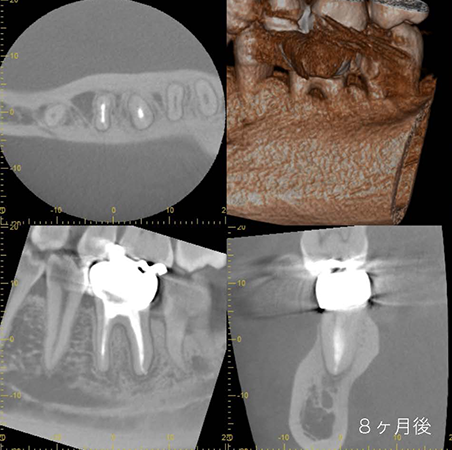

今回のケースは細菌の取り残しによって症状を引き起こしています。顕微鏡で精密な根管治療を行なったことにより8ヶ月後のCT像から透過像(骨吸収)が消失し、骨が完全に再生しています。適切な処置を行えば、歯を保存することができます。

歯をなるべく保存したい、他院で抜歯と診断された方は一度ご相談ください。

(※診査診断の結果、歯を保存できない場合があります)